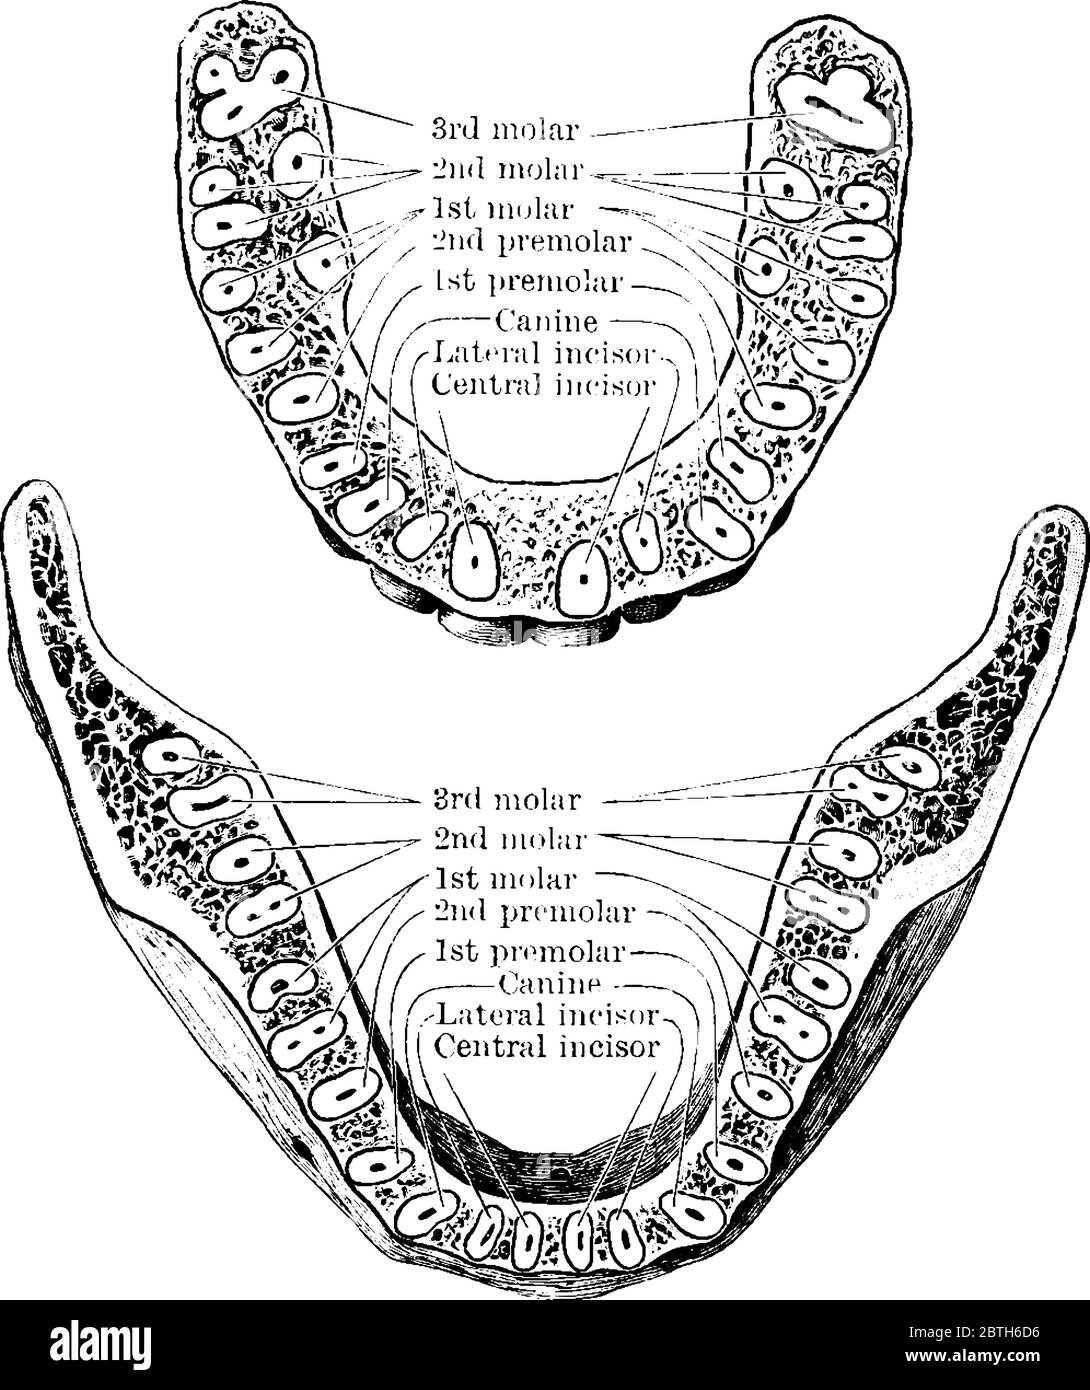

La section horizontale à travers les mâchoires supérieure et inférieure, montrant les racines des dents, dessin de ligne vintage ou illustration de gravure. Illustration de Vecteurhttps://www.alamyimages.fr/image-license-details/?v=1https://www.alamyimages.fr/la-section-horizontale-a-travers-les-machoires-superieure-et-inferieure-montrant-les-racines-des-dents-dessin-de-ligne-vintage-ou-illustration-de-gravure-image359337362.html

La section horizontale à travers les mâchoires supérieure et inférieure, montrant les racines des dents, dessin de ligne vintage ou illustration de gravure. Illustration de Vecteurhttps://www.alamyimages.fr/image-license-details/?v=1https://www.alamyimages.fr/la-section-horizontale-a-travers-les-machoires-superieure-et-inferieure-montrant-les-racines-des-dents-dessin-de-ligne-vintage-ou-illustration-de-gravure-image359337362.htmlRF2BTH6D6–La section horizontale à travers les mâchoires supérieure et inférieure, montrant les racines des dents, dessin de ligne vintage ou illustration de gravure.

Anatomie des dents, dents permanentes de la mâchoire supérieure et inférieure, illustration historique 1858 Banque D'Imageshttps://www.alamyimages.fr/image-license-details/?v=1https://www.alamyimages.fr/anatomie-des-dents-dents-permanentes-de-la-machoire-superieure-et-inferieure-illustration-historique-1858-image699872668.html

Anatomie des dents, dents permanentes de la mâchoire supérieure et inférieure, illustration historique 1858 Banque D'Imageshttps://www.alamyimages.fr/image-license-details/?v=1https://www.alamyimages.fr/anatomie-des-dents-dents-permanentes-de-la-machoire-superieure-et-inferieure-illustration-historique-1858-image699872668.htmlRM3CJHXMC–Anatomie des dents, dents permanentes de la mâchoire supérieure et inférieure, illustration historique 1858